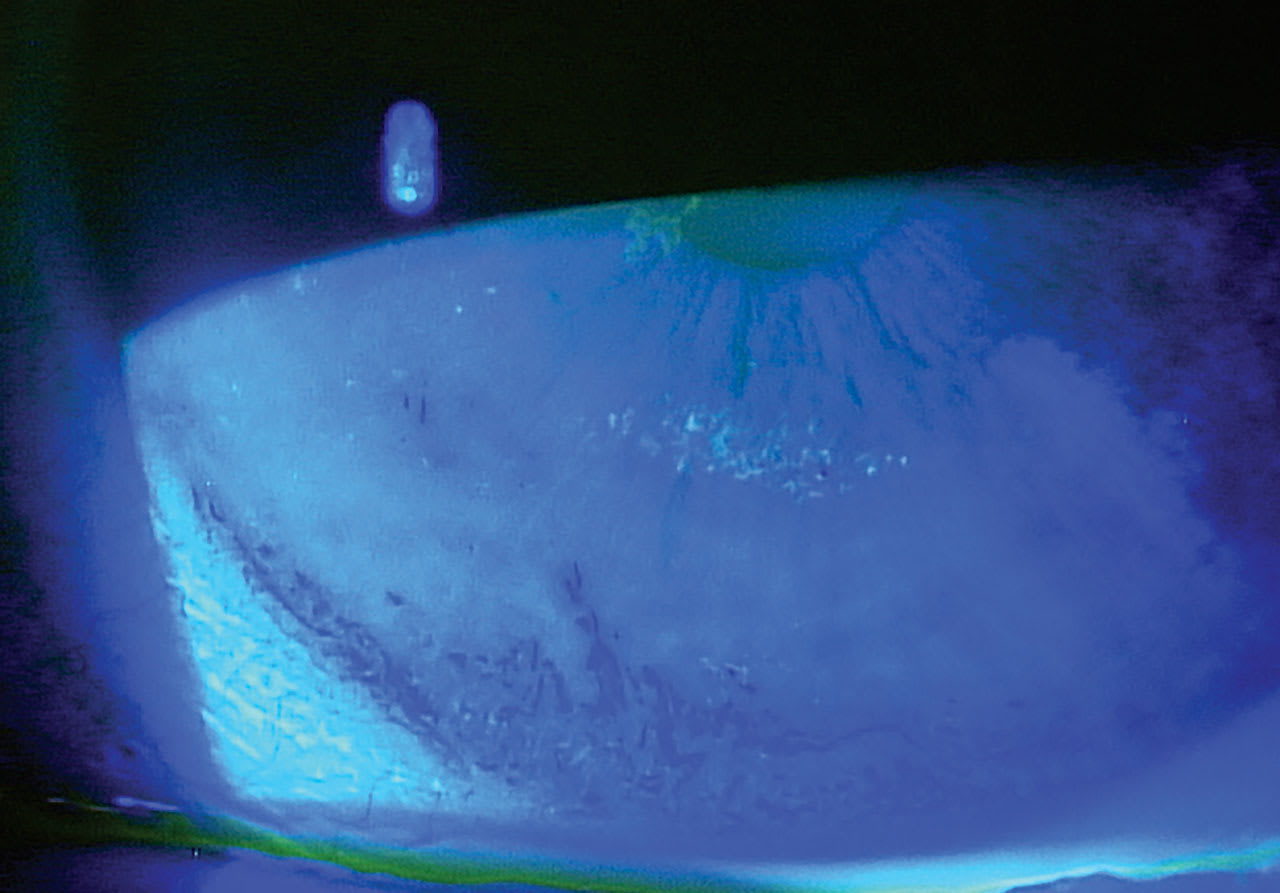

The most fundamental objective evidence of the presence of dry eye disease may be tear film hyperosmolarity2 and corneal and conjunctival staining (using fluorescein or vital dye staining, as in Figure 1), although neither signals for specific treatment options by itself. To simplify the many other clinical signs to look for and the corresponding treatments that address the specific issues found, the acronym MOIST can be used: Moisturize, Open/unblock, Inflammation control, Systemic concerns, and Tidying up the lids and lashes.

Improving tear quality by addressing lipid deficiency/evaporation is crucial in the management of the majority of dry eye patients. Meibography (Figure 2), investigative manual expression, interferometry, and tear breakup time (TBUT) can help identify the extent of this problem in each patient. In particular, meibography can be a powerful teaching tool to help convince patients of the need to address this aspect of their symptoms.